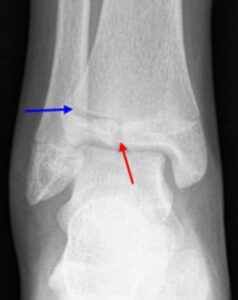

In children and adolescents, ankle fractures typically affect the tibia or fibula, often involving the growth plates—specialized areas of cartilage near the ends of long bones. Growth plates play a critical role in bone development, gradually hardening into solid bone as the child matures. However, because these growth plates are the last parts of the bones to solidify, they are particularly prone to injury and fractures.

As adolescents approach the end of their growth phase, growth plates begin to close and harden, making them susceptible to transitional fractures during this maturing stage. Two common types of transitional ankle fractures are triplane fractures and Tillaux fractures, which require specific treatment approaches depending on their severity and location (refer to the Treatment section for more details)